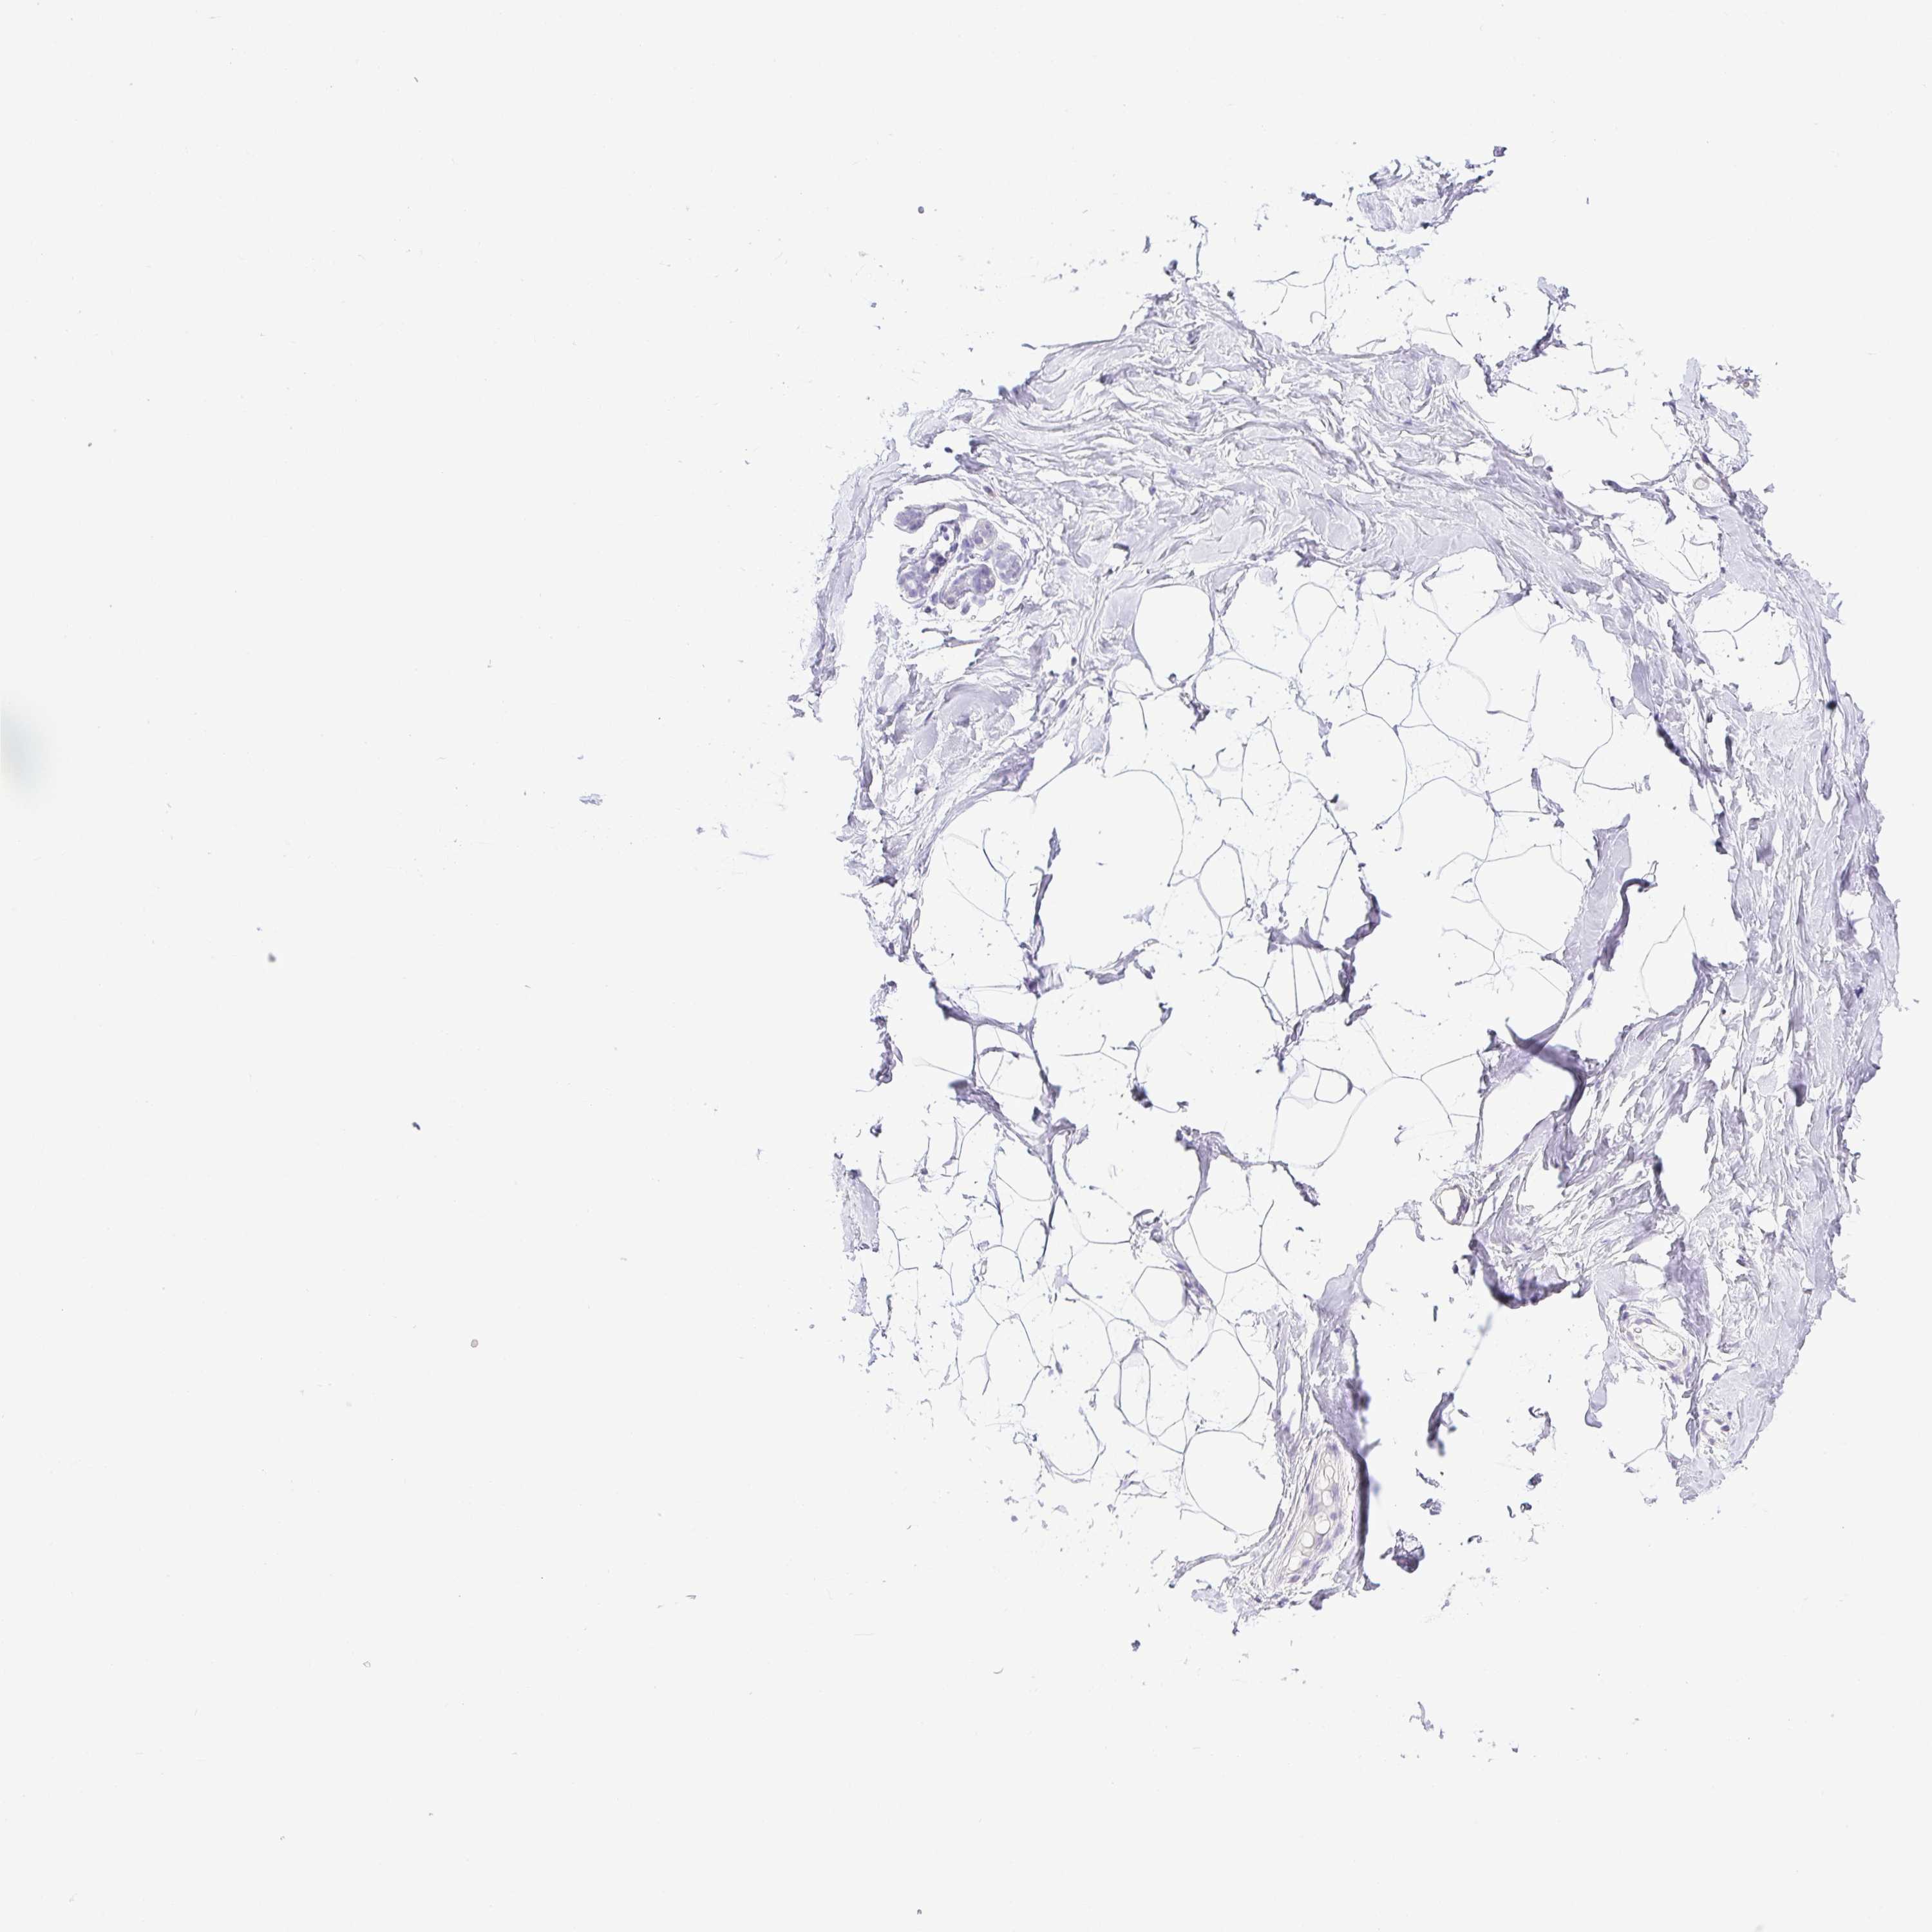

TISSUE PRIMARY DATA BREAST Show tissue menu

Breast

BREAST - Antibody stainingi

Antibody staining in the annotated cell types in the current human tissue is reported as not detected, low, medium, or high, based on conventional immunohistochemistry profiling in selected tissues. This score is based on the combination of the staining intensity and fraction of stained cells.

Each image is clickable and will lead to virtual microscopy that enables deeper exploration of all samples and also displays staining intensity scores, fraction scores and subcellular localization as well as patient and tissue information for each sample.

Antibody HPA018412Antibody HPA018430

Adipocytes Not detectedNot detected

Glandular cells Not detectedNot detected

Myoepithelial cells Not detectedNot detected